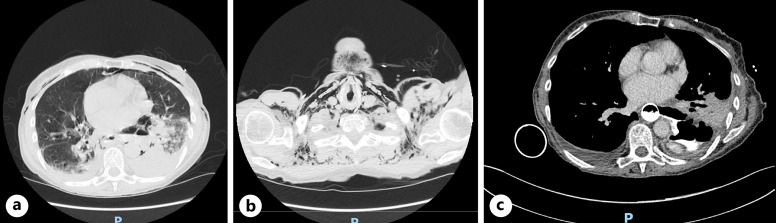

简介布尔哈韦综合征是一种罕见的疾病,发病率和死亡率都很高。及时干预可大大改善预后,手术是传统的主要治疗方法。最近,治疗性内窥镜技术的进步使人们对腔内真空疗法(EVT)越来越感兴趣,这是一种微创技术,可以对伤口进行清创和引流,促进肉芽组织的形成。EVT 具有积极的临床效果,包括与手术和支架治疗吻合口漏相比死亡率较低,其次是食道穿孔。EVT在欧洲已被广泛采用,但在英国却鲜有报道:我们报告了三例 Boerhaave 综合征病例,这些病例均使用 Eso-SPONGE ®(B.Braun Medical Ltd,英国谢菲尔德)EVT 成功治愈。EVT包括将聚氨酯海绵放入伤口腔内。首先对创腔进行评估,然后通过导管插入海绵,最后拔出导管。确认海绵位置,必要时进行调整。海绵通过经鼻引流管连接到持续负压吸引器,每 3-5 天更换一次。由于被认为不适合手术,所有 3 名患者都被转诊接受了 EVT。所有患者均恢复良好,并已出院回家:结论:对于不适合手术的波尔哈韦综合征患者,EVT 是一种有效的治疗策略。使用 Eso-SPONGE 有助于引流化脓灶和闭合缺损,使患者完全康复。我们的研究结果支持现有的证据,即 EVT 是治疗 Boerhaave 综合征的一种很有前景的方法。

Case presentations: We report three cases of Boerhaave syndrome, successfully managed with EVT, using the Eso-SPONGE ® (B.Braun Medical Ltd, Sheffield, UK). EVT involves the placement of a polyurethane sponge into the wound cavity. The cavity is initially assessed, then an overtube is introduced through which the sponge is inserted, and then the overtube is removed. Sponge position is confirmed and adjusted if necessary. The sponge is connected via a trans-nasal drain to continuous negative pressure suction and is changed every 3-5 days. Having been deemed surgically unfit, all 3 patients were referred for EVT. All patients made excellent recovery and were discharged home.